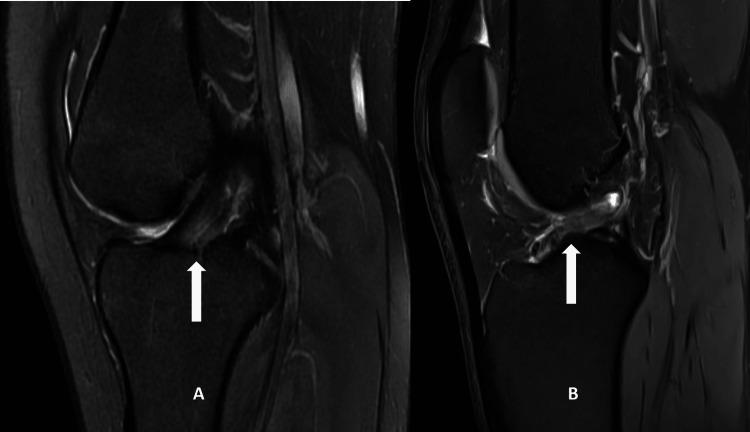

Background Over time, there has been a noticeable increase in anterior cruciate ligament (ACL) injuries. The current imperative is to anticipate predisposing factors and proactively prevent ACL injuries. The occurrence of ACL injuries has been linked to diverse factors associated with the morphology of the distal femur. Objectives Through this study, we aim to compare the anatomic variables of distal femur morphology such as notch width (NW), bicondylar width (BW), notch entrance width (NEW), and notch width index (NWI) between patients with ACL injuries and non-injured patients using MRI. We also aim to make a comparison of these factors between male and female genders to assess the gender variability. Material and methods A retrospective case-control study was conducted amongst patients who underwent MRI Knee scan for clinical suspicion of internal derangement during the study period. We selected the first 125 individuals who were found to have ACL injury in the MRI scans and selected another 125 individuals who had an intact ACL in the scans, to serve as controls in the study. Demographic information was retrieved from the hospital's electronic records, and the assessment of NW, NWI, BW, and NEW was conducted through a review of MRI sequences. They were then compared between the cases and control groups, as well as between male and female genders. Results The ACL-injured group exhibited statistically significant reductions in NW and NWI. While 17.39 mm was the mean NW among cases, 17.86 was the mean value among controls. Similarly, the mean NWI was 0.25 among patients with ACL injuries and 0.27 among controls. Gender-based comparisons also revealed statistically significant differences in NW and NWI measurements, where females were reported to have comparatively lower measurements. The mean NW for males and females in the injured group were 18.26 mm and 15.40 mm, respectively, while it was 18.71 mm and 16.90 mm, respectively, in the control group. In the case of NEW, males in the injured group had a slightly higher value (21.33 mm) than the controls (20.65). Females on the other hand exhibited a lower mean value of NEW in ACL-injured group (18.51 mm) in comparison to the non-injured (18.79 mm). BW did not seem to show a significant difference between the two groups. Conclusions In the studied population, ACL injuries demonstrated a higher occurrence in individuals with a narrow femoral intercondylar NWI. If any of these characteristics are identified in an MRI, it may be helpful to identify individuals who are at a higher risk of developing ACL injuries and may thereby help in planning preventative strategies.

目的 通过本研究,我们旨在使用MRI比较ACL损伤患者与未受伤患者之间股骨远端形态的解剖学变量,如髁间窝宽度(NW)、双髁宽度(BW)、髁间窝入口宽度(NEW)和髁间窝宽度指数(NWI)。我们还旨在比较这些因素在男性和女性之间的差异,以评估性别变异性。

结果 ACL损伤组的NW和NWI在统计学上有显著降低。病例组的平均NW为17.39mm,对照组为17.86mm。同样,ACL损伤患者的平均NWI为0.25,对照组为0.27。基于性别的比较还显示NW和NWI测量值在统计学上有显著差异,据报道女性的测量值相对较低。损伤组男性和女性的平均NW分别为18.26mm和15.40mm,而对照组分别为18.71mm和16.90mm。在NEW方面,损伤组男性的值(21.33mm)略高于对照组(20.65mm)。另一方面,ACL损伤组女性的NEW平均值(18.51mm)低于未受伤组(18.79mm)。两组之间BW似乎没有显著差异。